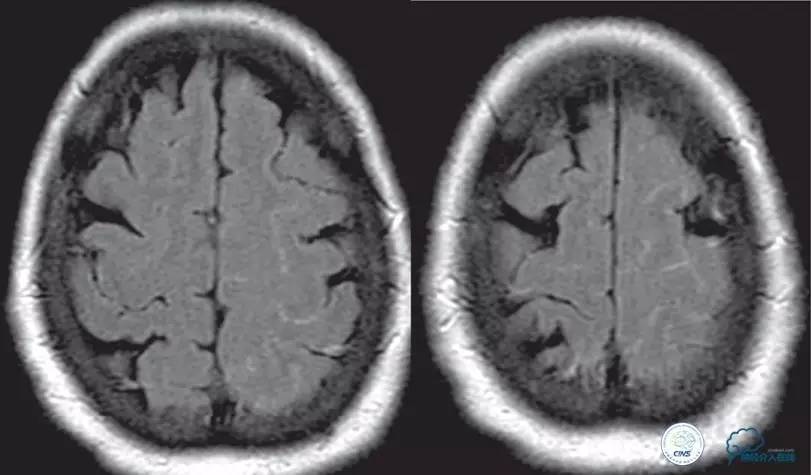

▼2015-06-05颅脑MRI

▼颅脑CT

▼2015-06-13颅脑CT

患者症状稳定,遗留有失语及右侧肢体活动不灵。